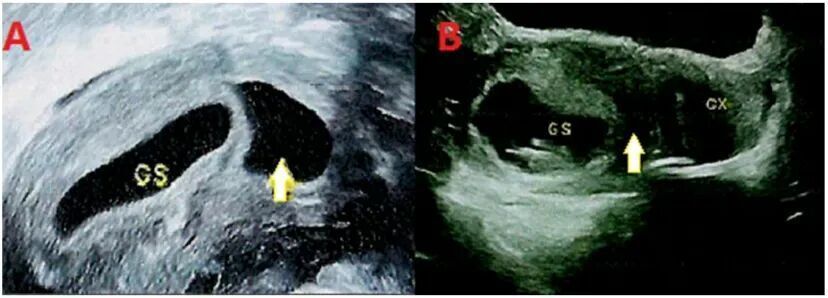

在上述产前检查案例中,通过回溯孕早期超声记录,研究者发现这名孕妇在孕7-9周时,子宫内曾出现短暂的“无回声区”,随后消失——这被推测是“消失的双胞胎”的残留痕迹,孕妇最初怀的异卵双胎在极早期融合,形成了携带两套基因组的嵌合体胎儿。

图片

图3:该案例中孕妇早孕期超声检查结果:(A)妊娠7+2周超声图像;(B)妊娠9+2周超声图像,GS为孕囊,黄色箭头所示区域为无回声区。| 图源:参考文献[2]